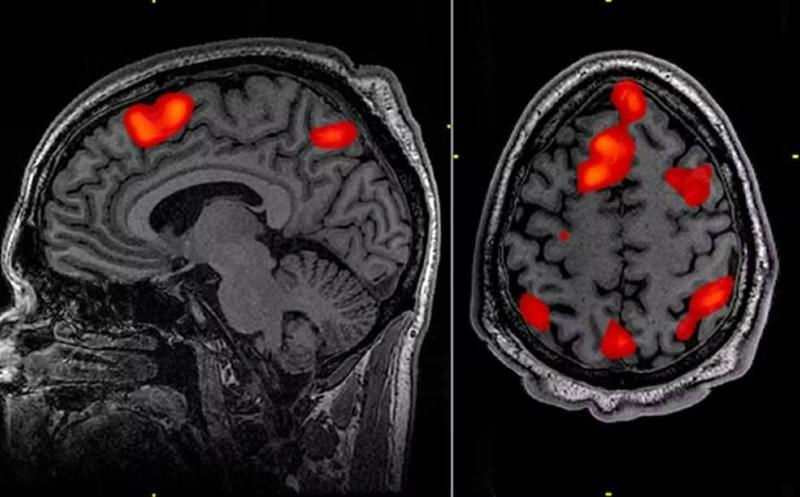

A doença de Huntington é causada por uma mutação no gene da huntingtina, que leva à produção de uma proteína tóxica para os neurônios. A condição provoca perda progressiva de funções motoras, cognitivas e comportamentais, resultando em dependência e morte, geralmente em até 20 anos após o início dos sintomas.